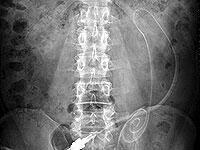

写真1は 70 歳、男性、糖尿病で慢性心不全の患者ですが、直腸に便塊がありカテーテルが持ち上げられ排液されませんでしたが、浣腸して注排液がスムースになりました。